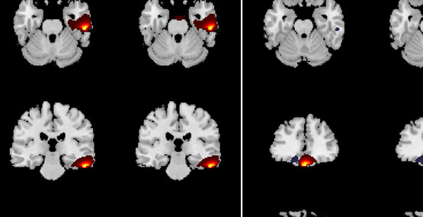

In the last two decades, unsupervised latent variable models---blind source separation (BSS) especially---have enjoyed a strong reputation for the interpretable features they produce. Seldom do these models combine the rich diversity of information available in multiple datasets. Multidatasets, on the other hand, yield joint solutions otherwise unavailable in isolation, with a potential for pivotal insights into complex systems. To take advantage of the complex multidimensional subspace structures that capture underlying modes of shared and unique variability across and within datasets, we present a direct, principled approach to multidataset combination. We design a new method called multidataset independent subspace analysis (MISA) that leverages joint information from multiple heterogeneous datasets in a flexible and synergistic fashion. Methodological innovations exploiting the Kotz distribution for subspace modeling in conjunction with a novel combinatorial optimization for evasion of local minima enable MISA to produce a robust generalization of independent component analysis (ICA), independent vector analysis (IVA), and independent subspace analysis (ISA) in a single unified model. We highlight the utility of MISA for multimodal information fusion, including sample-poor regimes and low signal-to-noise ratio scenarios, promoting novel applications in both unimodal and multimodal brain imaging data.